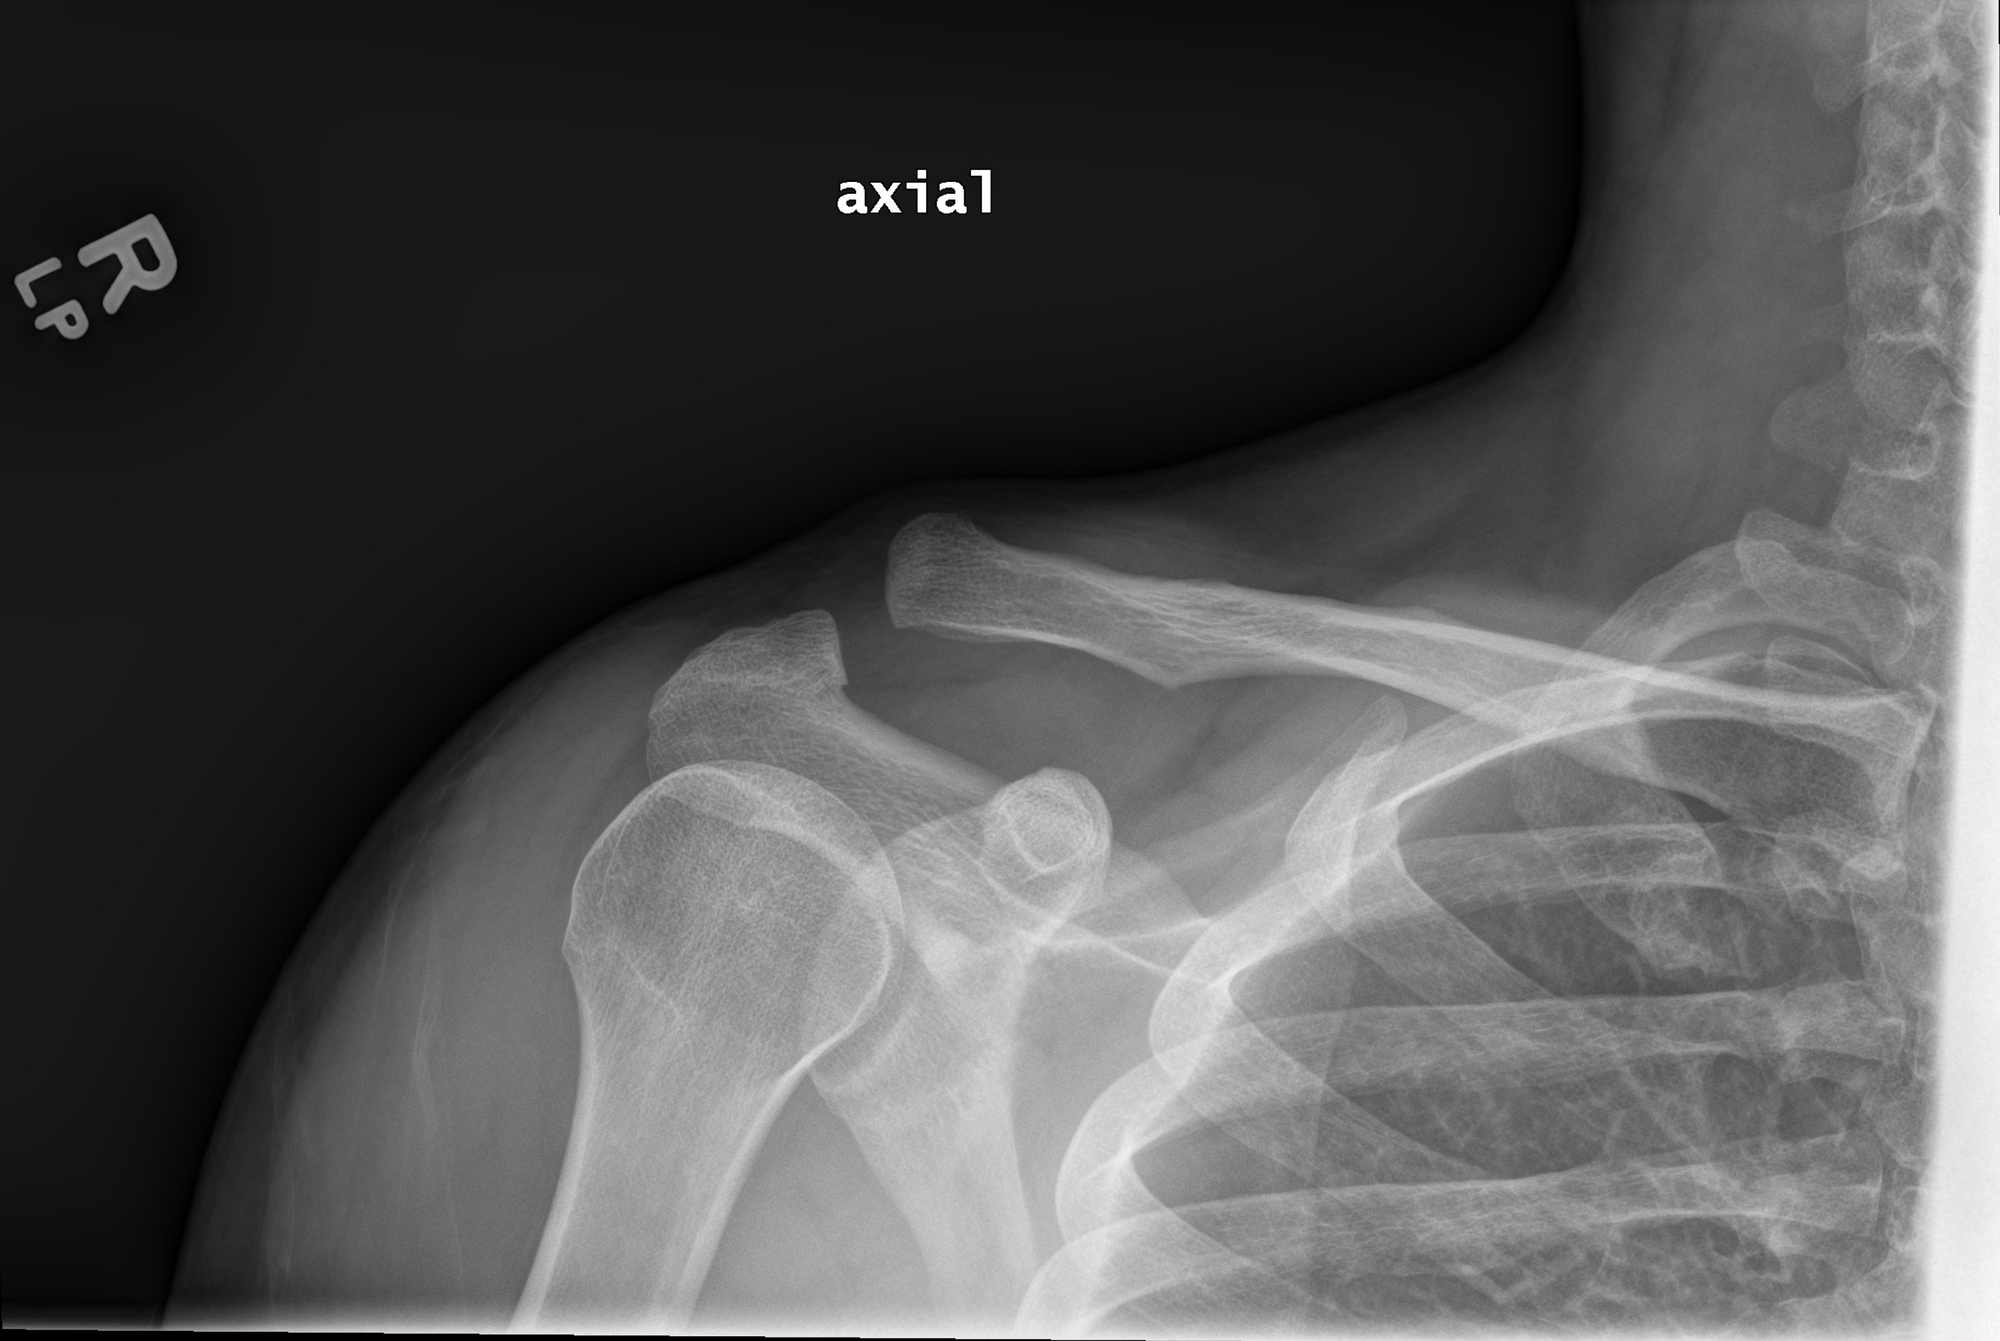

Mammoth ER was great, and I learned I had an AC separation grade 3. Strong AF bones, nothing broke, just ripped all the ligaments and whatever is in there that holds that bone in place. Most people just learn to live with it fine and a couple months later it doesn’t bother them seemed to be the advice. The nurse had done the same a few years before. The doctor as well. A followup visit in Truckee really steered me away from considering surgery - many people had worse issues as a result. They just haven’t figured this one out yet. Happy to report at the end of the year I’m basically back to full power, with a weird bone that sticks out, but pullups remain difficult and I’m not too eager to get on the mtb again.